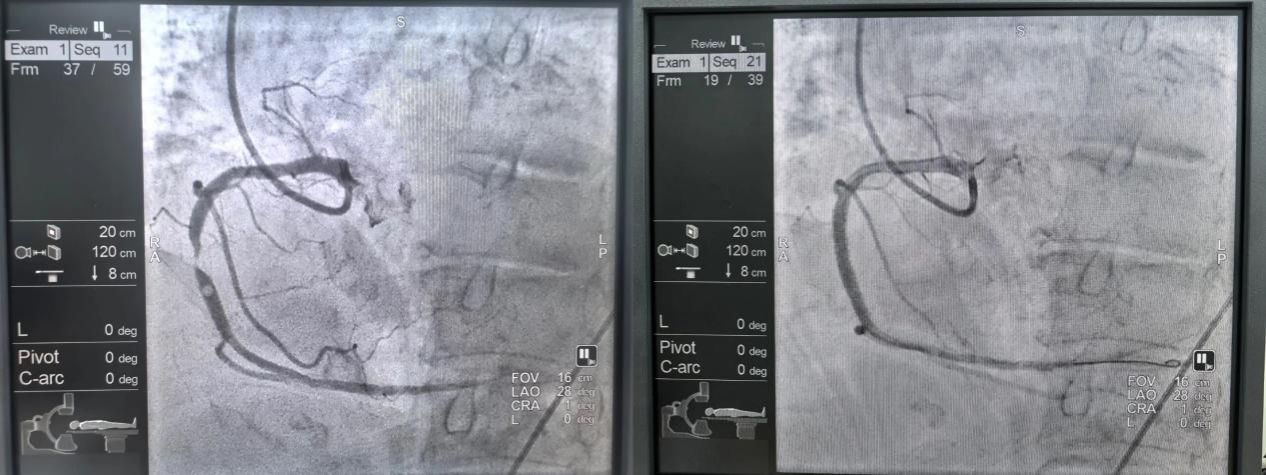

新疆医院成功开展频发性室性早搏射频消融术,以精准微创的技术为患者重启了平稳的心律,展现了医院在复杂心律失常诊断与介入治疗方面的综合能力,标志着医院心律失常诊疗迈入精准介入治疗的新阶段。

新疆医院成功为一位90岁高龄的急性冠脉综合征患者实施急诊介入手术。针对患者超高龄、超高危的状况,以及复杂的血管条件—右冠开口变异、前降支完全闭塞、右冠狭窄达99%,团队经严谨评估,精心准备,精准植入支架,此次超高难度手术的成功,标志着医院在急危重症及复杂冠心病诊疗领域实现了重要突破。